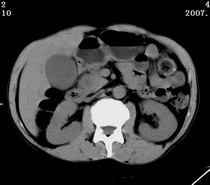

以下是引用zjzjr在2007-9-15 22:24:00的发言:[br]胰头钩突略饱满,肝内外胆管略扩张,胆囊积水.建议增强扫描.

以下是引用代课学生在2007-9-16 10:20:00的发言:[br]胆总管中段以上胆管均示扩张,考虑胆总管下段/胰头部病变,建议增强或micp检查。